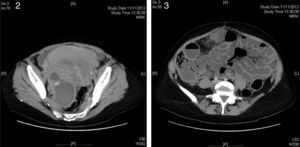

En la exploración, se encontraba normotensa, afebril, con palidez mucocutánea. Presentaba importante distensión abdominal y peritonismo generalizado. La exploración ginecológica fue normal. Las pruebas de laboratorio revelaron leucocitosis con neutrofilia del 87% y anemia leve con bioquímica, coagulación y sedimento de orina normales. En la ecografía transvaginal (fig. 1) únicamente destacaba una imagen quística en fosa ilíaca derecha de 86×45mm, de trabeculado fino, sin tabiques ni papilas, con una calcificación en su polo craneal, indicativa de quiste dermoide. La TC abdominopélvica (figs. 2 y 3) mostró una lesión quística lobulada de dimensiones superponibles, de probable dependencia anexial derecha con contenido líquido, pared gruesa, lisa y bien delimitada, con una calcificación milimétrica en su interior, marcada dilatación de asas intestinales sin presencia de tránsito, indicativa de íleo adinámico y una pequeña cantidad de líquido libre entre asas y adyacente al fundus uterino.